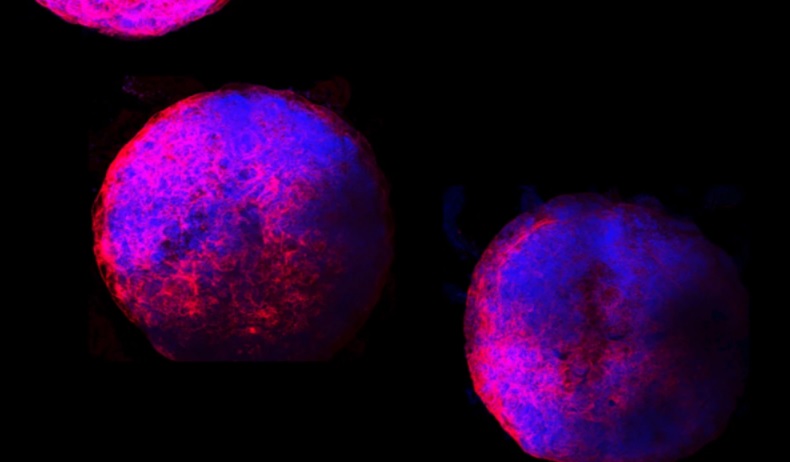

Фото: Michigan State University

К шестому дню миниатюрные сердца начали биться, а к пятнадцатому – превратились в сферы шириной около 1 мм.

Команда говорит, что выращенные в лаборатории мини-сердца подробно показывают, как развивается плод человеческого сердца. К шестому дню органоиды начали биться, а к 15 дню они превратились в сферы шириной около 1 мм со сложными внутренними камерами. Они также содержали все основные типы сердечных клеток.